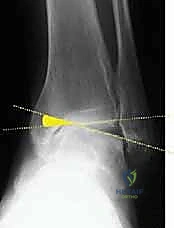

2. التصوير بالأشعة السينية بوضعية الوقوف (Weight-bearing X-rays)

هذا هو حجر الأساس في التشخيص. الأشعة العادية والمريض مستلقٍ لا تظهر الحجم الحقيقي للتشوه. يطلب الدكتور هطيف صوراً خاصة والمريض يحمل وزنه كاملاً على قدميه.

* المنظر الأمامي الخلفي (AP View): لتقييم المسافة المفصلية وتحديد زاوية سطح الساق (Tibial Anterior Surface Angle - TAS).

* منظر سالتزمان (Saltzman View): وهو منظر إشعاعي متخصص جداً لتقييم محاذاة الكعب الخلفي بالنسبة لمحور الساق، وهو أمر حاسم في التخطيط الجراحي.